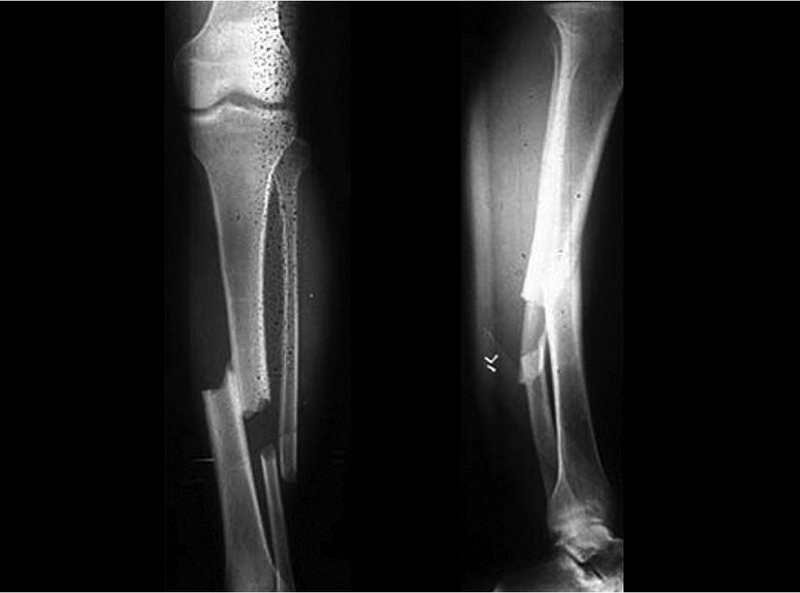

Gãy xương mác là hiện tượng xương mác bị tổn thương, có thể do nhiều nguyên nhân như tác động mạnh, tai nạn, va chạm hoặc chấn thương cụ thể khác. Gãy xương mác có thể là gãy ở nhiều vị trí, như phần đầu xương, cuối xương hoặc gãy giữa xương mác.

Tình trạng gãy xương mác hở tương đối phức tạp và có nhiều mức độ khác nhau. Phổ biến nhất là xương gãy hở xuyên qua da, dẫn đến tổn thương mô mềm, chảy máu, mất máu nhiều ở bệnh nhân gãy xương mác. Trường hợp bị gãy xương mác hở tương đối dễ nhận biết và gây đau đớn nhiều hơn cho bệnh nhân.

Nguyên nhân dẫn đến gãy xương mác hở thường do tai nạn, va chạm mạnh hoặc té ngã từ độ cao lớn xuống nền cứng. Đây cũng được nhận định là trường hợp gãy xương mác tương đối nghiêm trọng, bệnh nhân cần được sơ cấp cứu kịp thời, hạn chế nhiễm trùng và tiêm ngừa uốn ván là điều rất cần thiết.

Thực tế, gãy xương mác hở thường có nhiều mảnh xương vụn đâm vào mô mềm gây đau đớn, tăng khả năng nhiễm trùng nên cần thiết phải mổ để gắp xương ra, cố định xương bằng thanh nẹp kim loại và ốc vít chuyên dụng để kéo xương về đúng lại vị trí ban đầu.